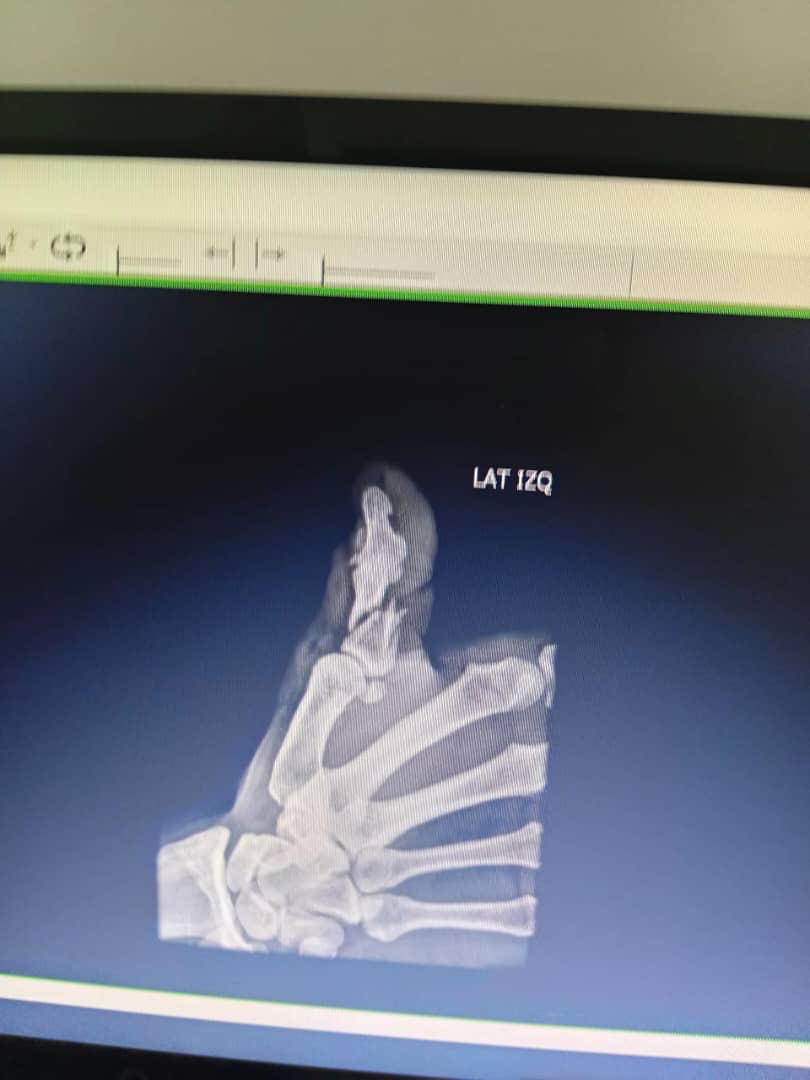

Unfortunately, while changing a tire, I suffered a serious accident that resulted in a severe fracture to one of my fingers. The injury was so serious that I required emergency surgery to prevent the finger from being amputated.

Lamentablemente, mientras cambiaba una rueda, sufrí un accidente grave que me causó la fractura severa de un dedo. La lesión fue tan seria que tuve que someterme a una cirugía de emergencia para evitar que me amputaran el dedo y perderlo por completo.